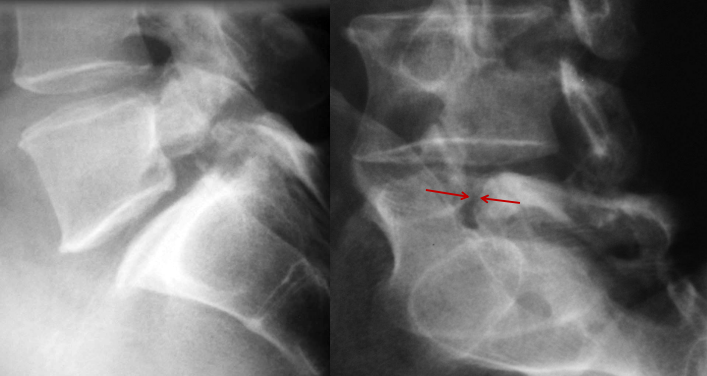

当椎弓狭部出现崩裂时(峡部裂),在狗颈部出现一条线状透亮影,宛如戴了一个项圈,这种征象就是我们在临床工作中经常见到的“狗戴项圈征”,是椎弓狭部裂的直接X线征象,引起椎体向前滑脱,称为脊柱真性滑脱(椎体滑脱、脊柱滑脱),导致腰椎失稳。好发于腰4、5椎体,以腰5椎体更多见。

狗戴项圈征,腰5椎弓狭部裂,腰5椎体真性向前滑脱(I°)

狗戴项圈征,腰5椎弓狭部裂,腰椎侧位未见明显滑脱征象